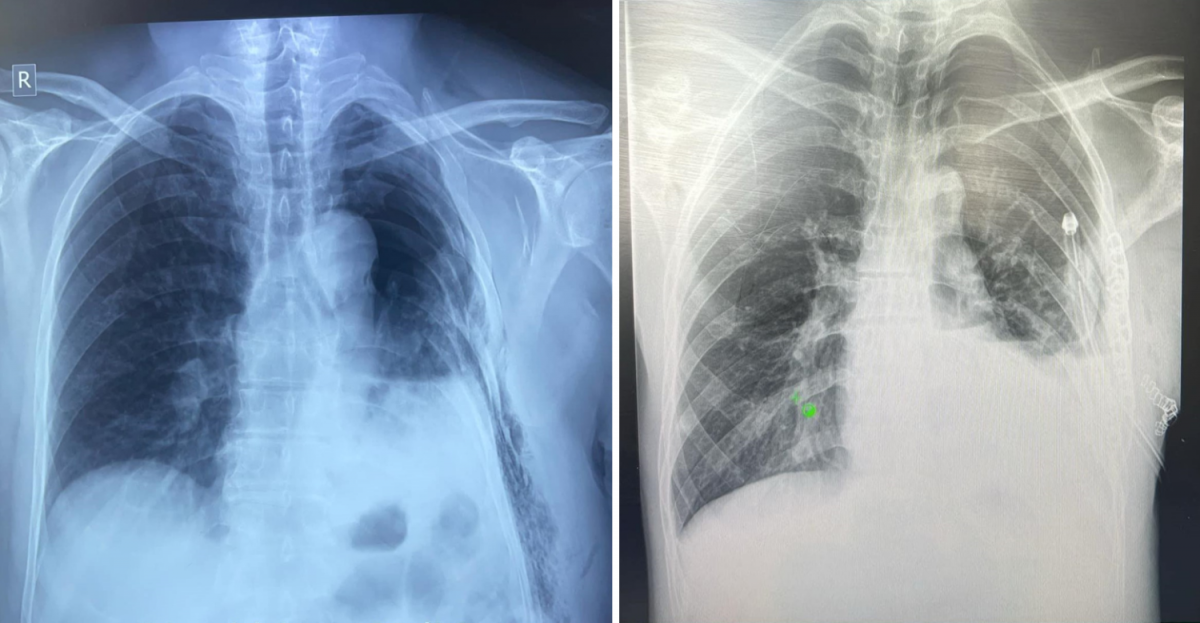

Тухайлбал, Ховд аймгийн Бүсийн оношилгоо эмчилгээний төвийн гэмтлийн эмч Б.Батбулган, мэдээгүйжүүлгийн эмч Б.Батбаатар, мэдээгүйжүүлгийн сувилагч Н.Ганчулуун, мэс заслын сувилагч Ц.Отгонжаргал, туслах сувилагч Д.Ууганцэцэг нартай хамтран авто ослын улмаас цээжний хөндийн хавсарсан хүнд гэмтэлтэй өвчтөнд яаралтай мэс засал эмчилгээ хийжээ.

Мөн Баян-Өлгий аймгийн эрүүл мэндийн төвийн гэмтлийн эмч А.Еркебек, мэс заслын эмч Е.Мурат, мэдээгүйжүүлгийн эмч Б.Ержан, мэдээгүйжүүлгийн сувилагч Ж.Еркетай, мэс заслын сувилагч Лена, асрагч Манар нарын хамт уушгины няцрал, олон хавирганы тогтворгүй хугаралтай, амьсгалын дутагдалд орсон өвчтөнд мэс засал эмчилгээг амжилттай хийсэн аж.